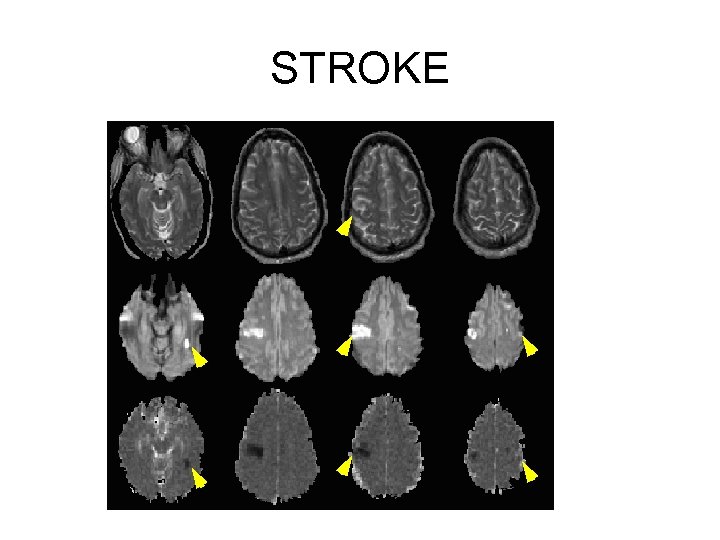

STROKE